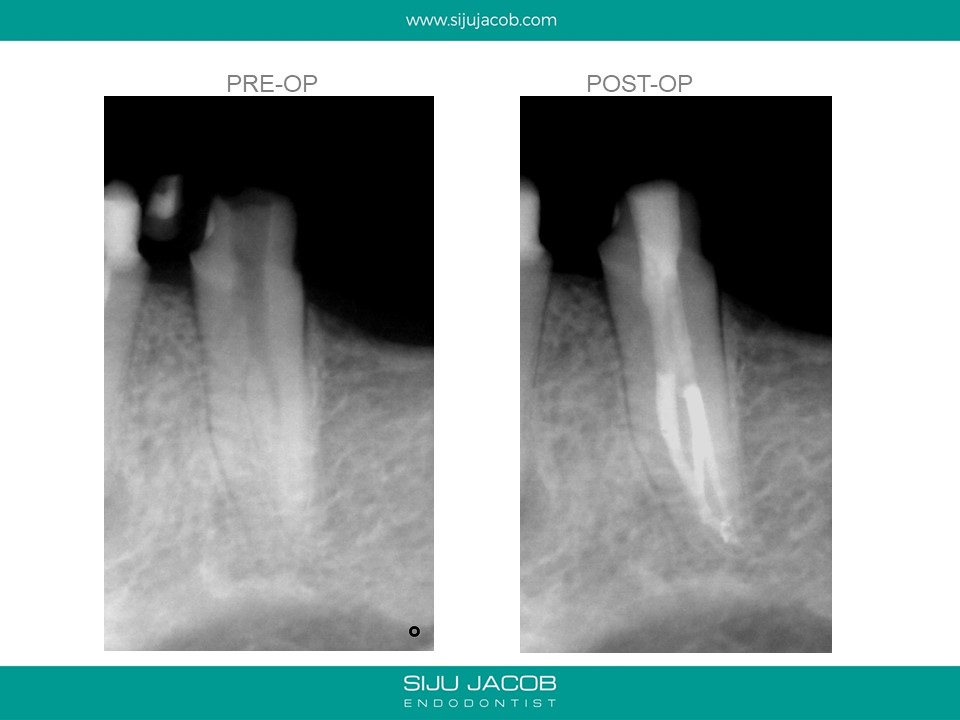

This was referred by a clinician who started the case thinking it was a regular premolar. Looking at the radiograph that the referral e-mailed me, I was expecting a Two-canalled premolar. The master-cone radiograph showed the lack of centricity of the two canals i had discovered. I went back in and found the third canal.